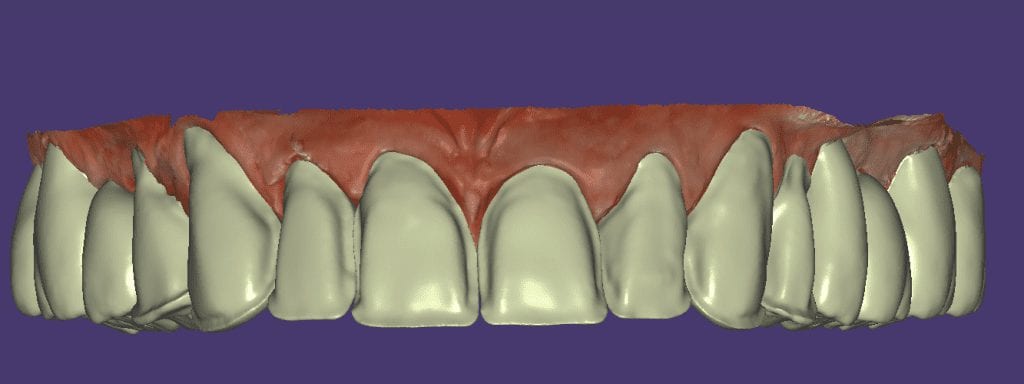

The digital models were then imported into a third party software where a library of tooth morphologies are available for the clinician to choose from.

Once the appropriate library is chosen, the digital wax ups are performed. In the subsequent photos you can see the transparent overlay of the wax-ups to the original position of the existing dentition

Once the case is designed to the ideal vertical dimension then multiple shells can be fabricated for treatment. The wax up model can be uniformly reduced by .5mmm’s circumferentially and a temporary shell can be designed. Once the teeth are prepared, these shells can be relined and seated onto the preps.